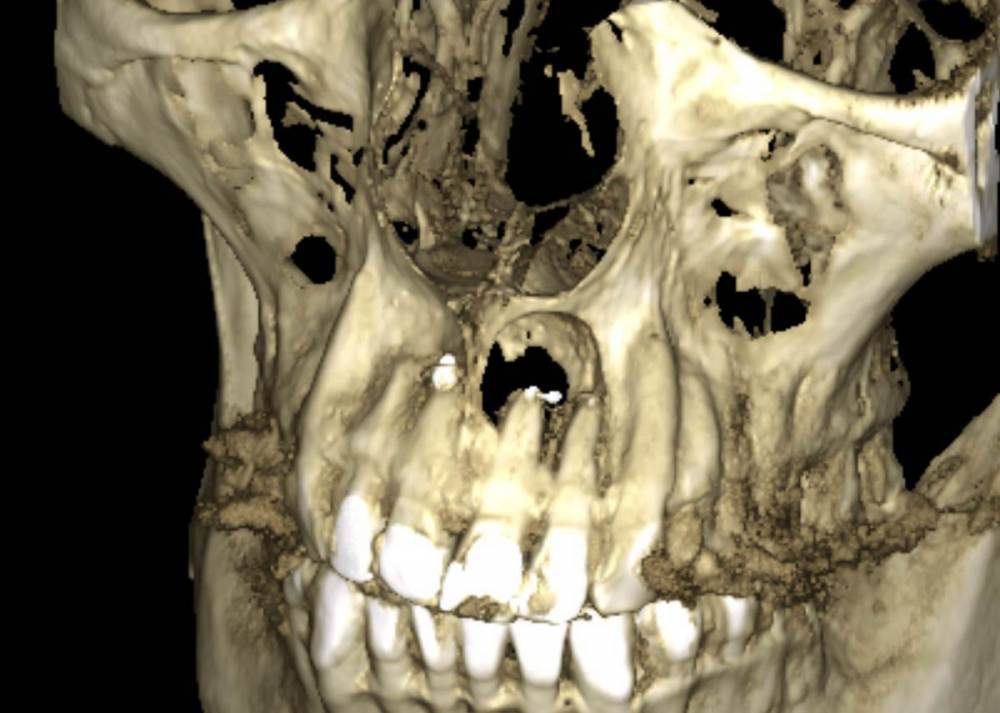

АнтонТЛТ Опубликовано 27 сентября, 2024 Поделиться Опубликовано 27 сентября, 2024 Ну как-то так прошла операция, резекция трёх зубов, 3д реконструкции последнего кт нет в телефоне Дефект сквозной был 6 Ссылка на комментарий